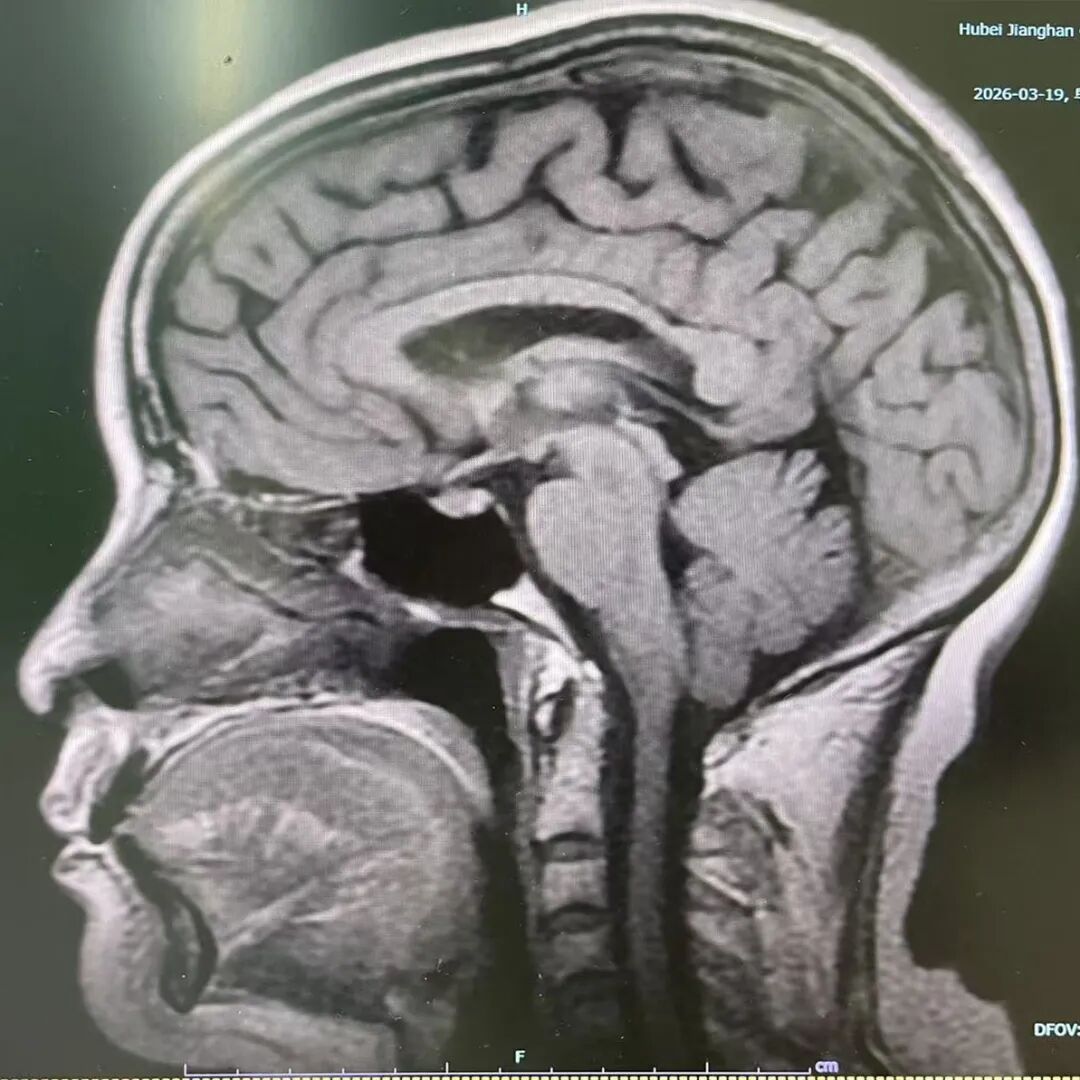

磁共振是利用强磁场和射频脉冲,激发人体水分子中的氢原子共振,再通过接收信号重建图像,由于完全不依赖X射线,所以没有辐射风险。

头部磁共振影像(右图)

这项检查对肌肉、神经、韧带、脊髓等软组织的分辨能力很强,常用来诊断关节损伤、脑肿瘤、椎间盘突出等。

虽然这项检查无辐射风险,但因为检查过程中患者处于强磁场范围,体内有心脏起搏器、人工耳蜗等铁磁性金属植入物者严禁检查,且金属物品绝对不能带进检查室。